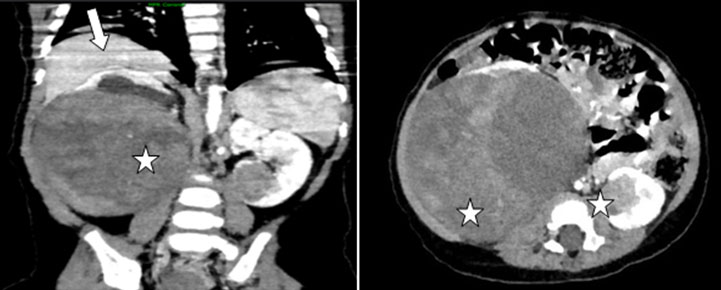

The abdominal ultrasound showed a hyperechoic and heterogeneous bilateral renal mass and demonstrated hypoechoic cortical nodularity related to NB lesions (Figure 1). The abdominal CT scan after intravenous contrast agent injection showed bilateral renal masses measuring 11 cm on the right and 3 cm on the left, hypodense evoking a bilateral nephroblastoma (Figure 2). There was no invasion of the renal vein and the inferior vena cava. However, NB lesions could not be detected.

Figure 2: Coronal and axial abdominal CT after contrast injection in nephrogenic phase demonstrating bilateral nephroblastoma presenting as a heterogeneous solid mass (asterisk) with the “claw sign” (arrow).

Imaging findings of nephroblastoma depend on the different components of the tumor (necrosis, hemorrhage, calcification, and fat). The characteristic signs are the presence of a solid mass well defined with pseudocapsule, realizing a rind or “claw” of renal parenchyma surrounding the tumor [6].